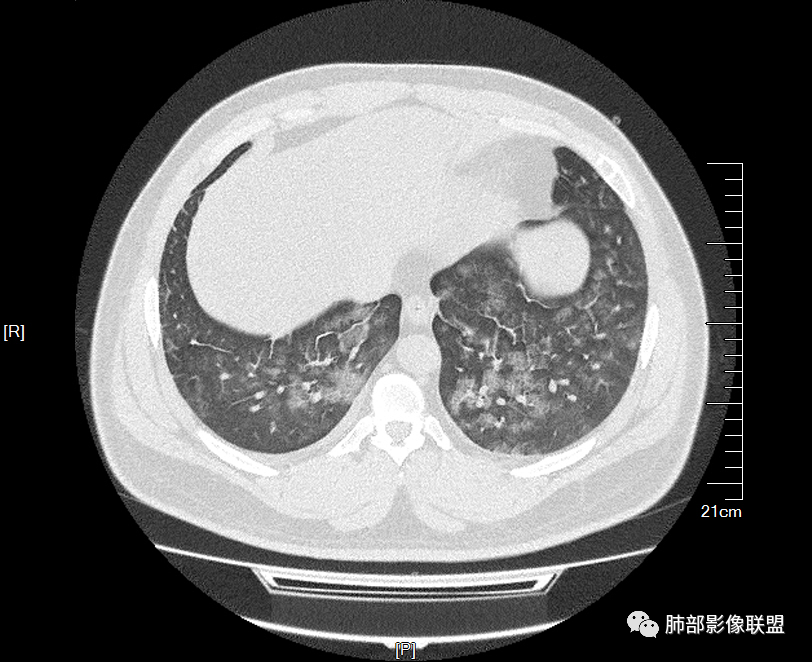

双肺多发弥漫性磨玻璃结节影,大小不一,形态不规则,部分融合,支气管未见明显扩张,部分血管束略增粗,叶裂胸膜增厚,临床有痛风,左足痛6天,考虑:1:痛风结节(一般实性结节,很少磨玻璃结节影)2:血管炎?3:病毒性肺炎(水痘-疱疹肺炎?)

双肺多发腺泡结节及磨玻璃,小叶间隔增厚(大网格状),腺泡结节内及磨玻璃内可见细网格影(小叶内间隔增厚),影像表现符合肺泡出血改变,血肌酐升高,考虑肺肾综合征。鉴别肺水肿。

年轻男性,既往血肌酐升高,左足痛六天入院,有痛风及高血压病史。CT示双肺多发磨玻璃结节影,不规则,部分融合成团或片状,小叶间隔增厚,以双下肺为明显,叶间胸膜亦见增厚。考虑为1.Good-Pasture综合征。2.病毒性肺炎?3.肺水肿?

年轻男性,痛风史,高血压史,肌酐高,左足痛6天入院。胸CT:双肺多发弥漫性磨玻璃结节影,大小不一,部分融合,上中下肺都有,中内带多,胸膜下少。部分血管束略增粗,小叶内间隔、小叶间隔增厚,下肺明显,左室大。叶裂胸膜增厚。临床有痛风,左足痛6天,考虑:心衰、间质性肺水肿?弥漫性肺泡出血?鉴别:MPA,肺肾综合征,痛风结节等。

多发GGO结节,边界清,以全小叶、小叶中心为主:

GGO背景

小叶间隔增厚,无明显重力趋势

少量积液,脂肪肝

这里有一点重力趋势

中轴间质稍增厚

细网格也明显

中轴间质增厚,小叶间隔增厚,小叶内间质增厚,部分重力作用,双侧对称,胸水,按理淋巴道回流受阻有

肺水肿类病变有

问题是腺泡结节如何解释?